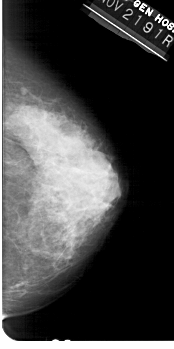

A_1449_1.RIGHT_MLO

RIGHT_CC LINES 5221 PIXELS_PER_LINE 2596 BITS_PER_PIXEL 12 RESOLUTION 43.5 NON_OVERLAY